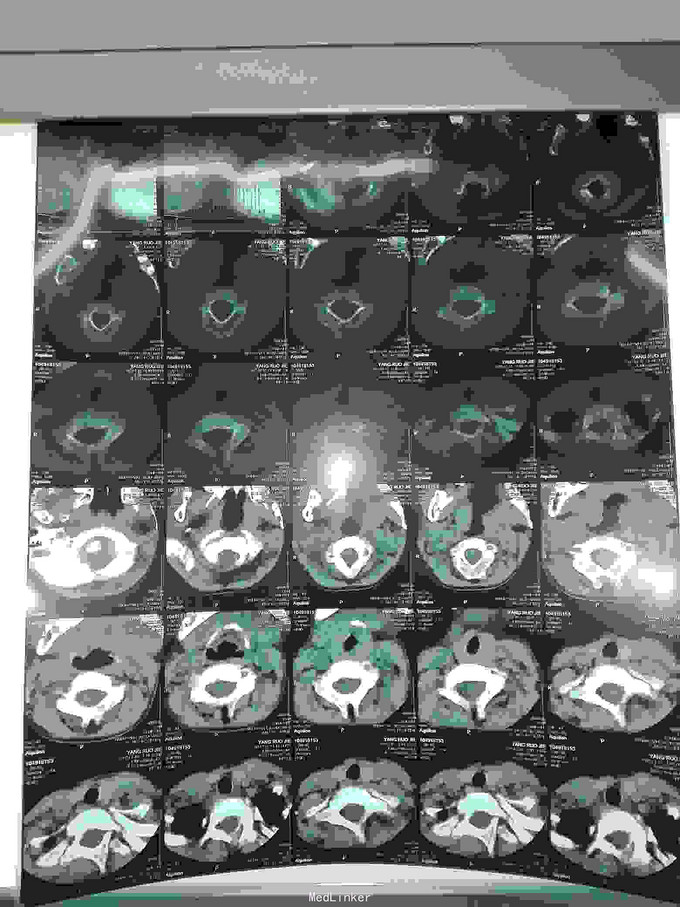

先天脊柱畸形

先天脊柱畸形8年。

严重脊柱畸形病例

先天性脊柱侧凸畸形

脊柱先天畸形